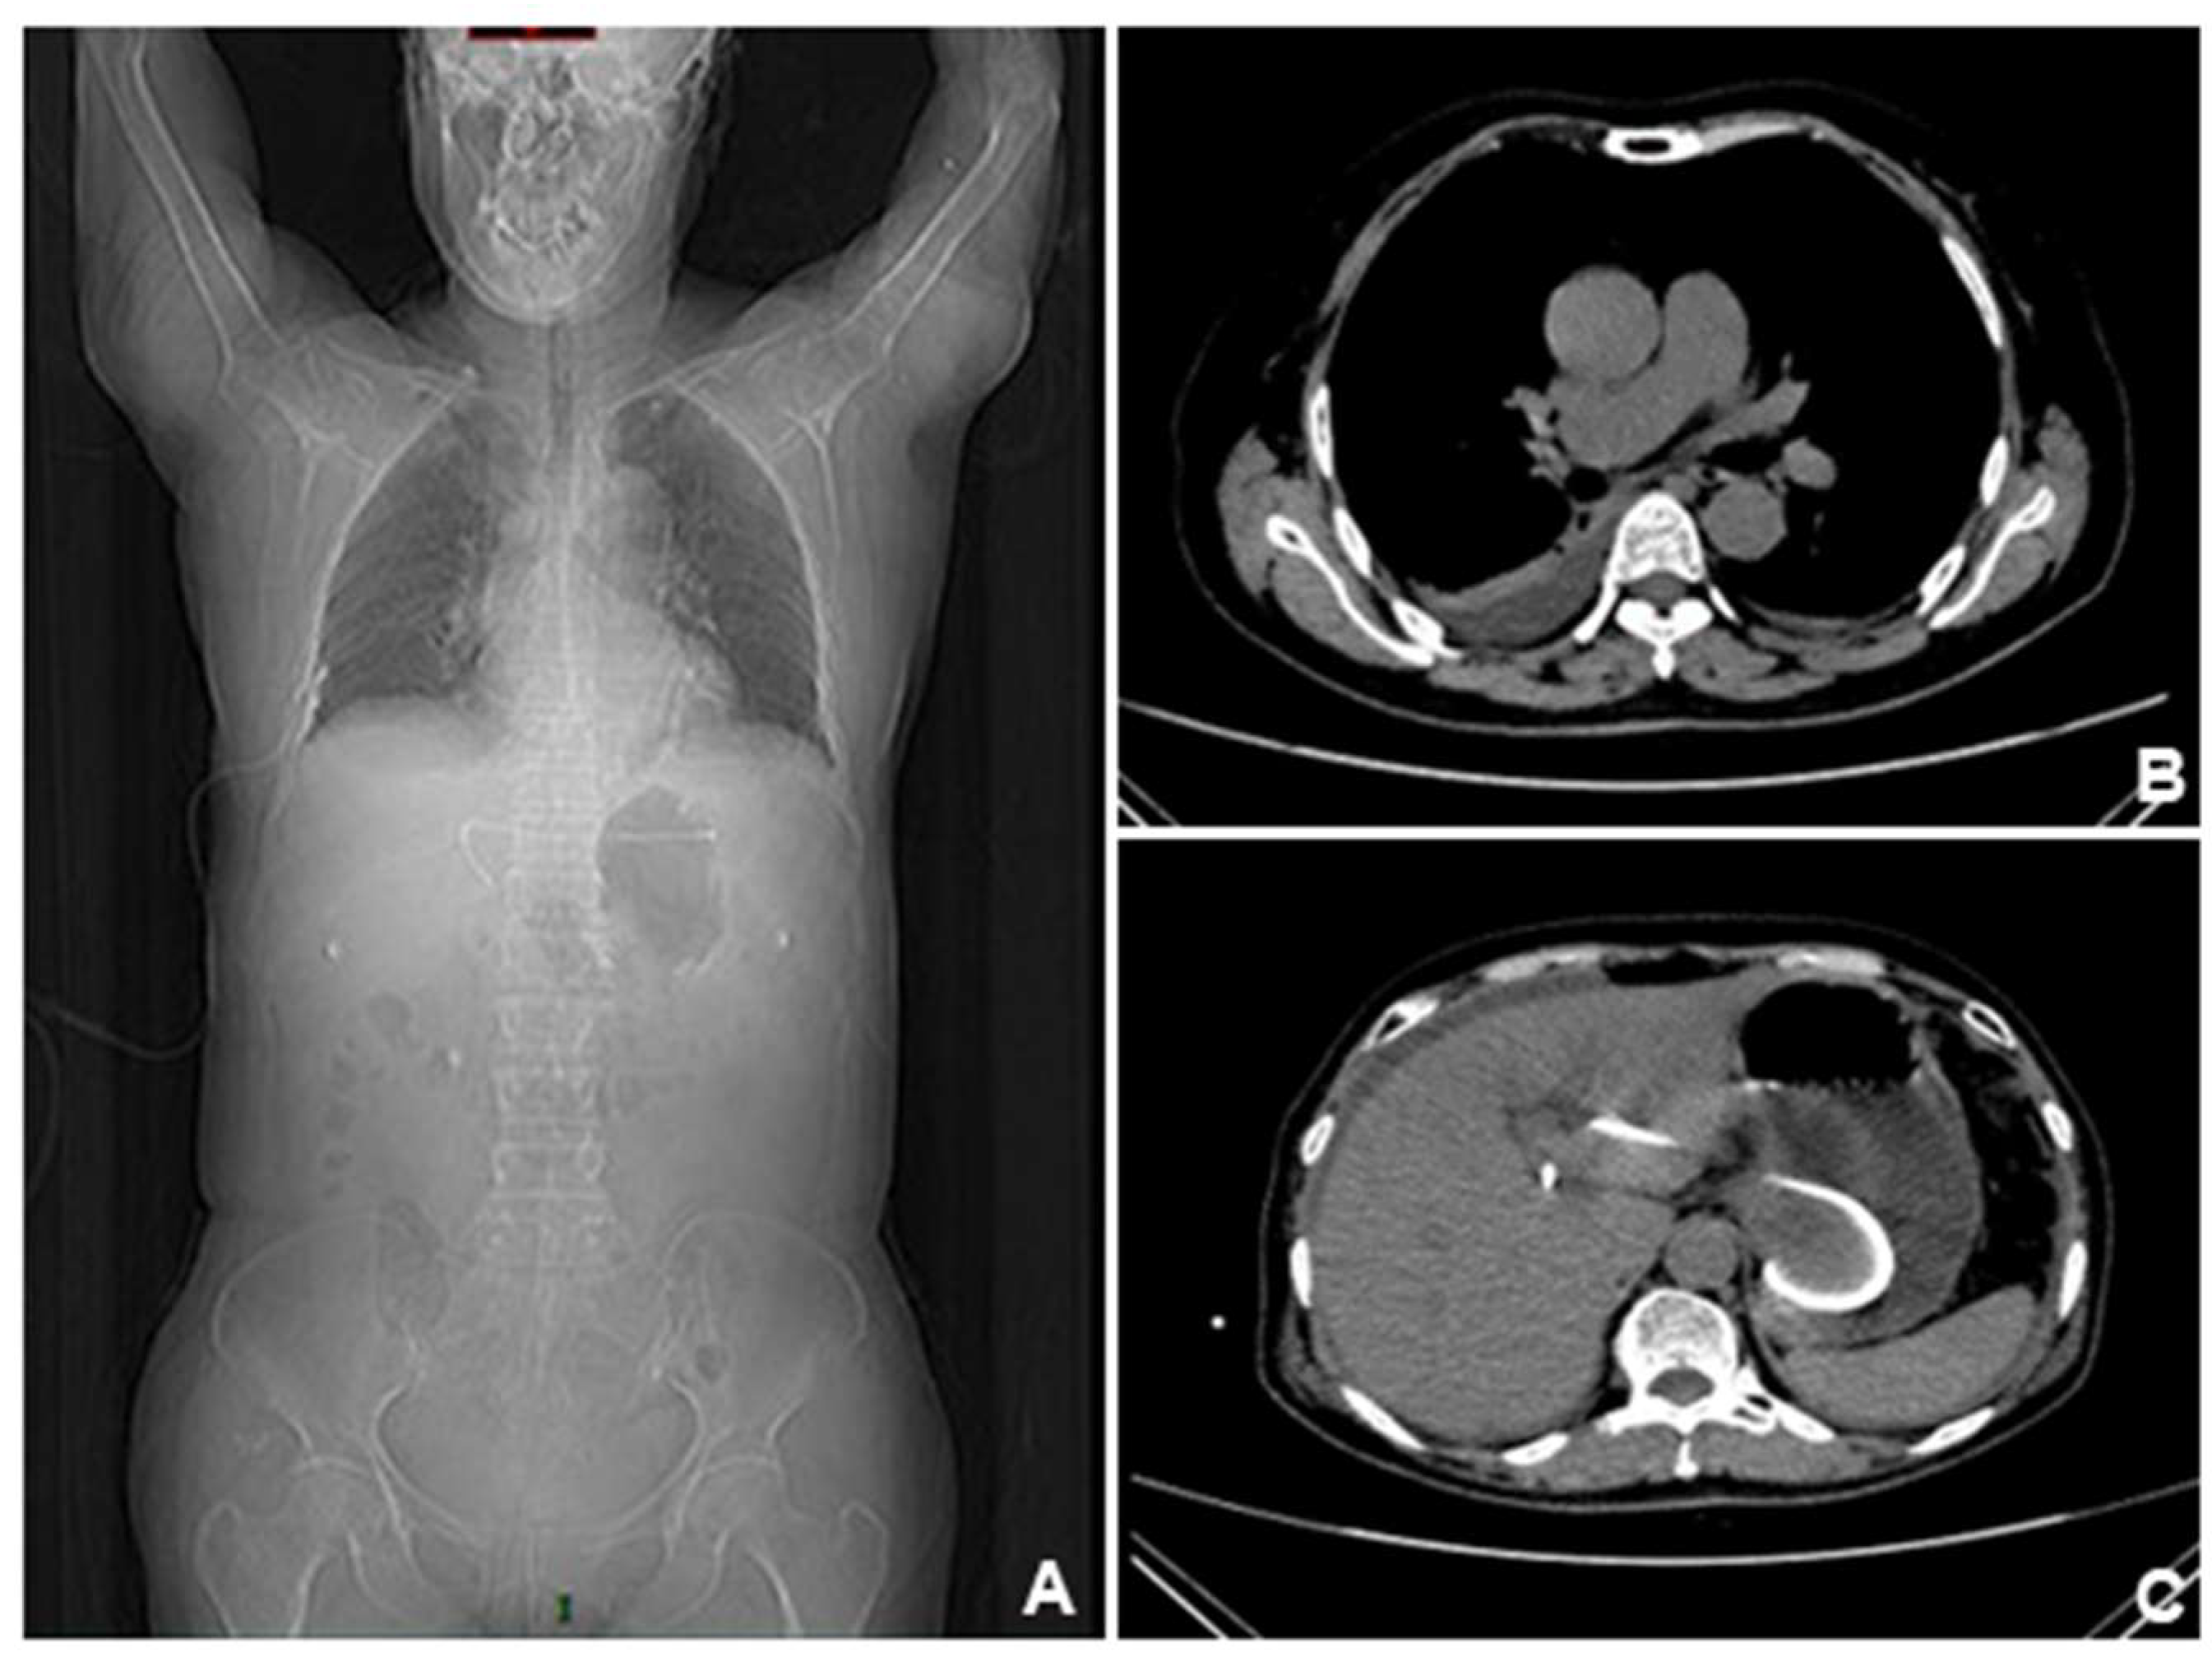

CT scan of the patient ten days after the CT scan in Figure4. (A). Previous pleural effusion was almost disappeared, but abdominal and pelvic ascites appeared. (B-C). Ascites gradually increased and accumulated around the liver. (D). The lesions were compartmentalized and encapsulated internally. The patient had developed complications of EUS-BD: biliary leak. Ultrasound-guided abdominal duct drainage was attempted, but failed due to high puncture difficulty and poor expected outcome. Based on the above presentation, we suspected that this patient had developed complications of EUS-BD: biliary leak. However, this complication is still insufficient to explain the color change of the urine, which appeared on every afternoon. It’s noteworthy EUS-BD has become the prior substitute for those who failed ERCP, and enhancing understanding of its process and potential risk and preventing its complications (which can be fatal such as stent migration) are of great importance to endoscopists. Despite a high clinical success rate, EUS-BD still may be associated with adverse effects in one-seventh of the cases. Therefore, postoperative surveillance after EUS-BD must be emphasized [3-5], for patients with abnormal laboratory findings or clinical manifestations, CT scans must be done to check for possible abnormalities such as stent migration, pneumoperitoneum, or fluid collection.